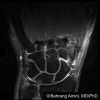

MRI에서 월상골과 삼각골의 변화를 관찰합니다.

MRI : 척골 충돌 증후군(Ulnar impaction syndrome)